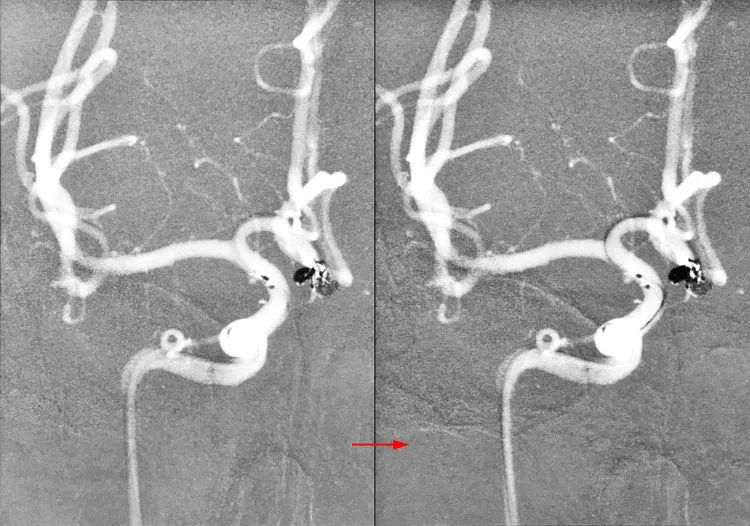

2017年4月5日行DSA+介入治疗。右颈内动脉造影显示右侧前交通动脉瘤,呈牛角形分叶(左图);左颈内动脉造影显示左侧大脑前动脉A1段发育稍差(右图)。拟行双微管技术栓塞,无须刻意保全前交通动脉。

右颈内动脉造影三维重建测量,公共瘤颈宽3.0 mm;大分叶3.4 mm×5.8 mm,可作为小型动脉瘤对待;小分叶2.3 mm×2.4 mm,可作为微小动脉瘤对待。